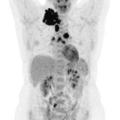

Tomographie par émission de positons : une place centrale dans le bilan et l'évaluation

La tomographie par émission de positons (TEP-scan) est une technique d’imagerie nucléaire fonctionnelle non invasive et désormais largement disponible. Elle est fondée sur l’utilisation d’un radiotraceur radio­actif ciblant un processus biologique, injecté au ­patient, dont la distribution peut ainsi ­être analysée à l’imagerie…

La démarche thérapeutique de première ligne a largement évolué ces dernières années, vers une optimisation du rapport bénéfice-risque. Que la présentation du lymphome de Hodgkin (LH) soit localisée ou avancée, le standard de traitement intègre désormais la tomographie par émission de positons (TEP) pour guider la stratégie, en…